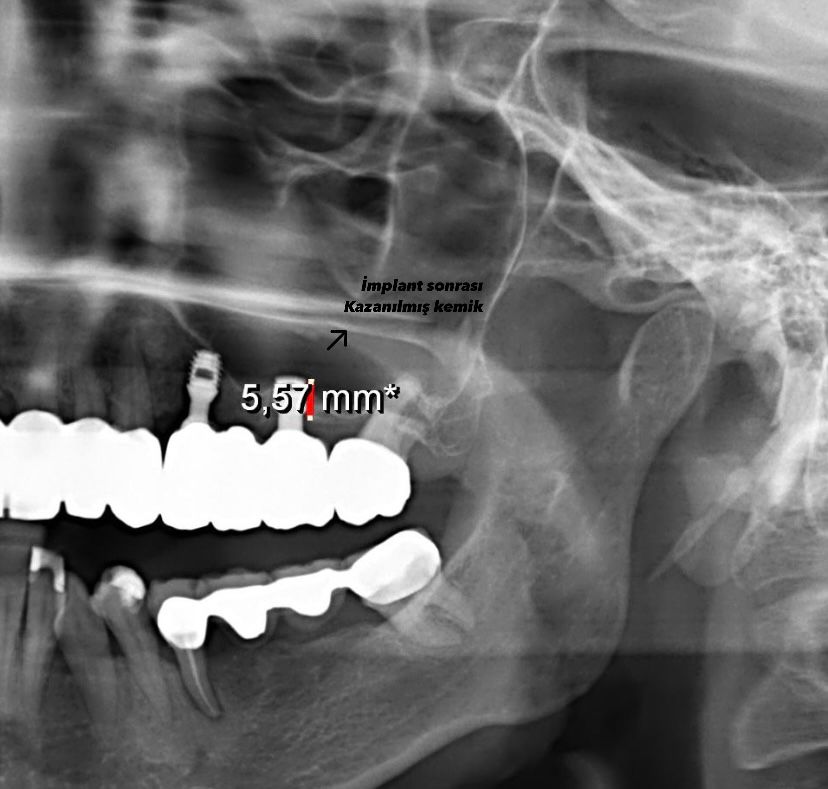

Zamanında tedavi edilmemesi nedeniyle birçok hastanın “Hocam, yıllar önce tedavi görmeye vakit ayıramadım” diyerek kendisine başvurduğunu aktaran Kayadelen, geçmişte bu gibi vakalarda köprü uygulamaları veya çıkarılabilir protezler tercih edilirken, artık hidroksiapatit yüzeyli implantlarla kaybedilen kemiğin kazanılmasının mümkün hale geldiğini ifade etti.

‘’Yeni geliştirilen kemik kaplı implantlar, çene kemiğinin erimesini durdurup, bölgeye yeniden kemik kazandırarak hastalara kalıcı ve sağlıklı dişlere kavuşma imkânı sunuyor. Sadece tek seferlik bir işlemle, hastaya implant yerleştiriliyor ve 4 aylık bekleme sürecinin ardından doğal diş formunda estetik bir yapı oluşturuluyor. Bu süre boyunca hastalar, ilgili bölgeyi boş bırakabiliyor ve hiçbir rahatsızlık hissetmeden günlük yaşamlarına devam edebiliyor. Süreç konforlu ve kesintisiz ilerliyor. Diş çekimi sonrası vakit kaybetmeden boşlukları doldurmak çok önemli. Ancak uzun yıllar geçmişse ve kemik erimesi ileri seviyedeyse, kemik kaplı implantlarla bu sorunu çözebiliyoruz. Bu yeni yöntem sayesinde, yıllar süren dişsizlik sorunları artık kolayca giderilebiliyor ve hastalar sağlıklı bir gülümsemeye yeniden kavuşabiliyor.’’